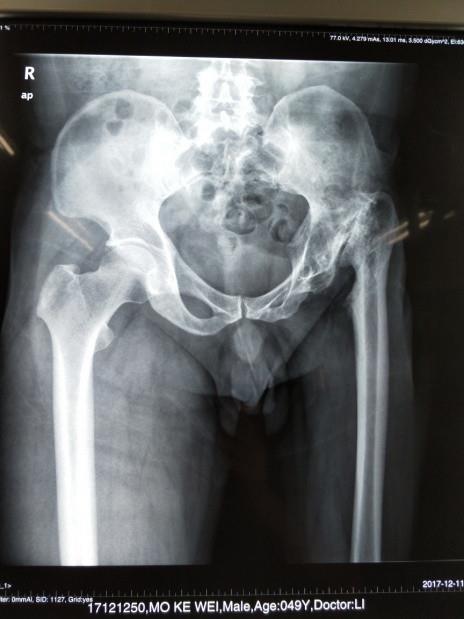

开展数字化技术,3D打印技术在骨科诊疗中的应用,提高骨科诊疗水平,获得广西科技厅重大专项建设项目。

开展人工髋、膝关节置换手术